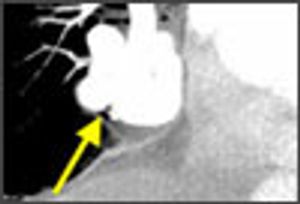

An 86-year-old woman presented with a 1-week history of worsening dyspnea, wheezing, and orthopnea. She denied chest pain, cough, or fever. She did not smoke cigarettes. Her oxygen saturation was 86% on 2 L/min via nasal cannula.